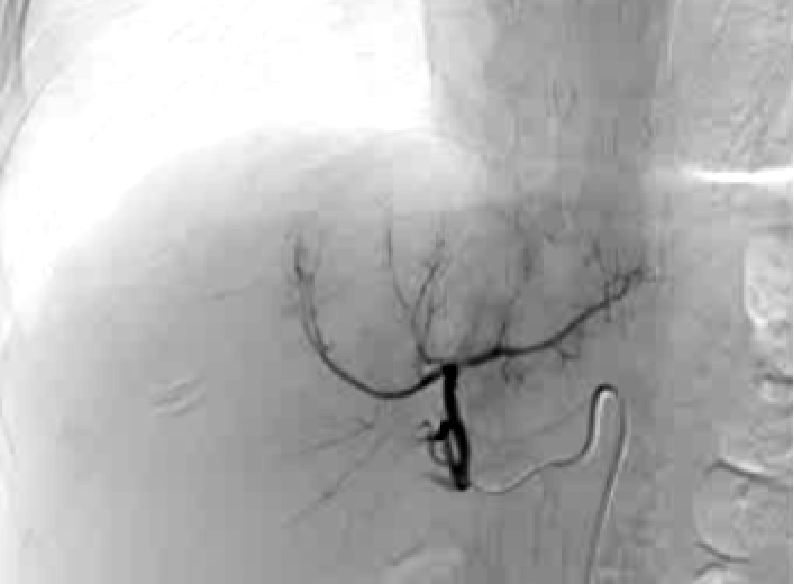

· 单中心、样本量小; 83 岁的女性,体重超标 40 毫米单发 ICC(S7-S8) 中肝静脉和右肝静脉浸润性,活检:非酒精性脂肪性肝炎(慢性肝病),马斯氏(MaS)病(30%)

考虑采用“三步策略 TARE→ PVE → Surgery”方案 剂量活性:1.56 和 3.16 GBq